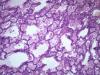

Подскажите как назвать данную пневмонию. По закону парных случаев, на данный момент у меня два разных случая с одинаковой морфологией. В морфологии в альвеолах эозинофильное содержимое, слущенные альвеолоциты, гигантские, многоядерные клетки, выраженный геморрагический компонент, местами немного лейкоцитов, свертки фибрина. Обширные свертки в бронхах. Очень похоже на вирусную, но как ее может назвать морфолог?

Интерстициально-десквамативная.

+ местами похоже на гиалиновые мембраны и в капиллярах межальвеолярных перегородок встречаются мегакариоциты.